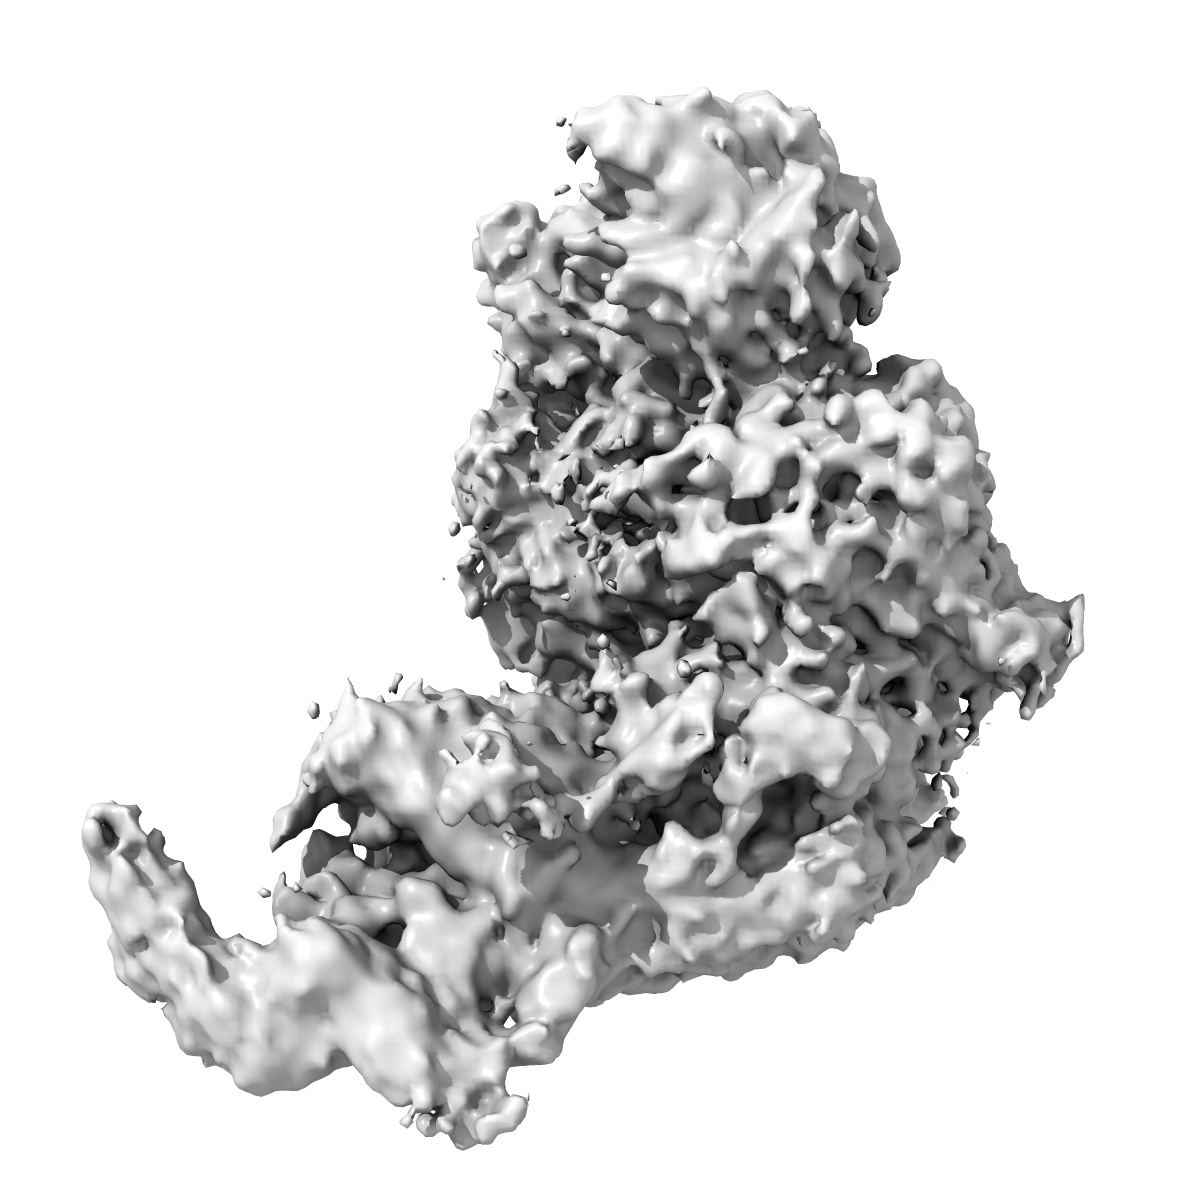

Cryo-EM structure of factor Va bound to activated protein C

Cryo-EM structure of coagulation factor Va bound to activated protein C.